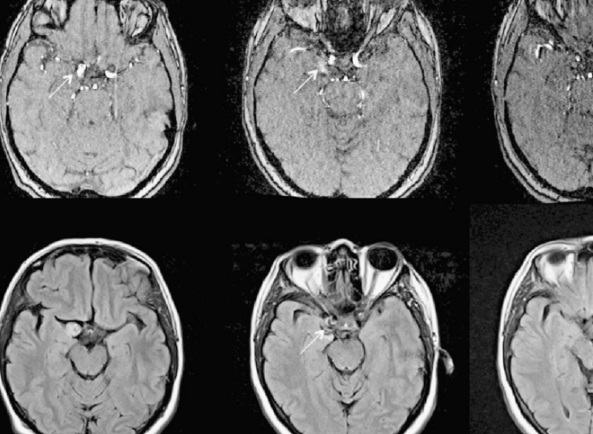

MRI란 무엇인가 (정밀 진단의 기준)

**MRI**는 자기장과 전파를 이용해 인체 내부를 매우 정밀하게 촬영하는 검사입니다.

이런 부분을 MRI는 정확하게 구분합니다.

✔ 실제 사용 사례

- 허리디스크 진단

- 뇌종양 검사

- 무릎 인대 파열

- 척추 신경 압박 확인